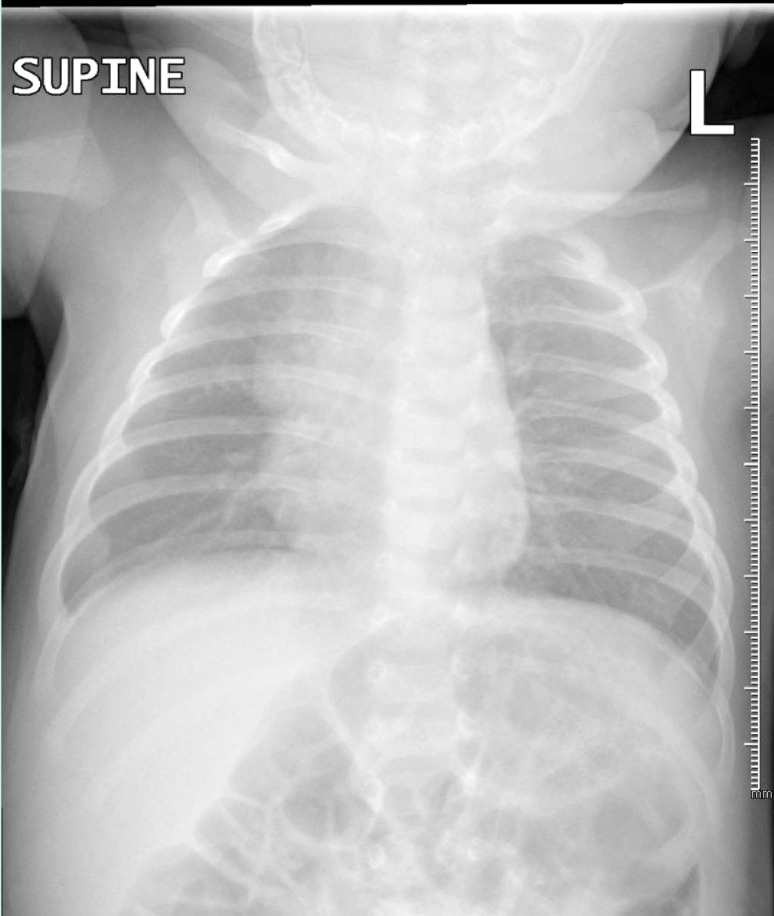

Abstract Image